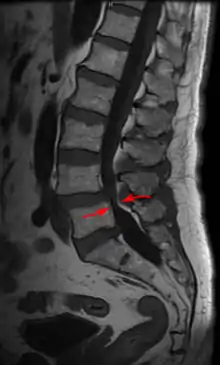

Lumbar spine showing advanced ankylosing spondylitis which can lead to spinal stenosis Lumbar spine showing advanced ankylosing spondylitis which can lead to spinal stenosis

MRI

MRI is the preferred method of diagnosing and evaluating spinal stenosis of all areas of the spine, including cervical, thoracic, and lumbar.[19][20] MRI is useful to diagnose cervical spondylotic myelopathy (degenerative arthritis of the cervical spine with associated damage to the spinal cord).[21] The finding of degeneration of the cervical spinal cord on MRI can be ominous; the condition is called myelomalacia or cord degeneration. It is seen as an increased signal on the MRI. In myelopathy (pathology of the spinal cord) from degenerative changes, the findings are usually permanent and decompressive laminectomy will not reverse the pathology. Surgery can stop the progression of the condition. In cases where the MRI changes are due to vitamin B12 deficiency, a brighter prospect for recovery can be expected.[22][23][24]